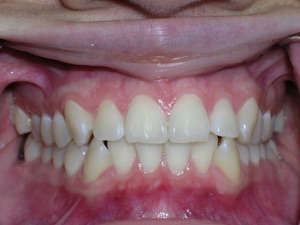

Here are the results. We used a bonded retainer on the bottom teeth.